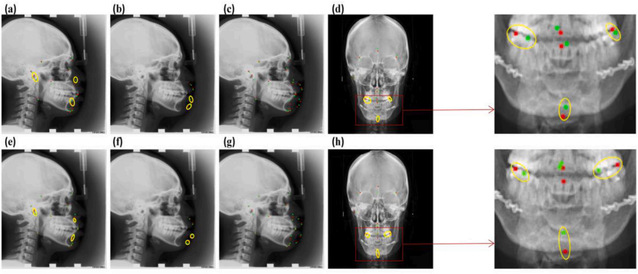

在头影测量分析中,头部标志的识别对正畸和正颌手术中颌面组织的解剖定位有重要贡献。然而,现有的方法存在精度低、识别过程繁琐的限制。在此基础上,论文提出了一种多尺度YOLOV3(MS-YOLOV3)算法,用于检测头部测量标志。经验证,相较于传统的YOLOV3方法,该方法具有较好的鲁棒性,侧位2 mm内检出率为80.84%,3 mm内为93.75%,4 mm内检出率为98.14%,前后位2 mm内检出率为85.75%,3 mm内检出率为92.87%,3mm,4mm内检出率为96.66%。结果表明,该模型可用于侧位和前后位的标记,可用于临床正畸和正颌手术。